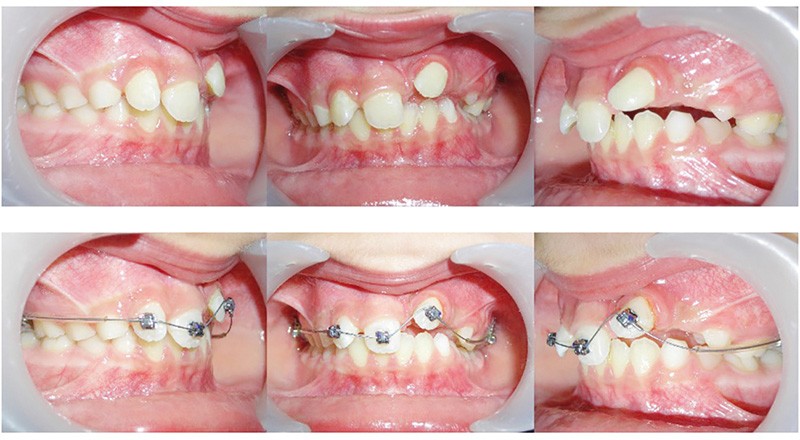

La gestion esthétique immédiate passe par un traitement orthodontique précoce, car la position de 22 (fig. 3) empêche toute restauration provisoire de l’édentement. Au vu du contexte, le choix thérapeutique se portera sur la simplicité, la rapidité, l’esthétique puis la réévaluation sur le long terme.

La 22 doit être remise sur l’arcade et le choix est fait de la mettre en lieu de 21 (fig. 4), puis de la maquiller pour temporiser en attendant l’évolution des autres dents définitives, et éviter le port d’une prothèse amovible transitoire (P.A.T.) tout en ramenant de l’os alvéolaire dans l’espace de 21.

L’interception dure 6 mois, et les attaches antérieures sont laissées en place et ligaturées (fig. 5) pour permettre une contention légère. On note la perte de la médiane.